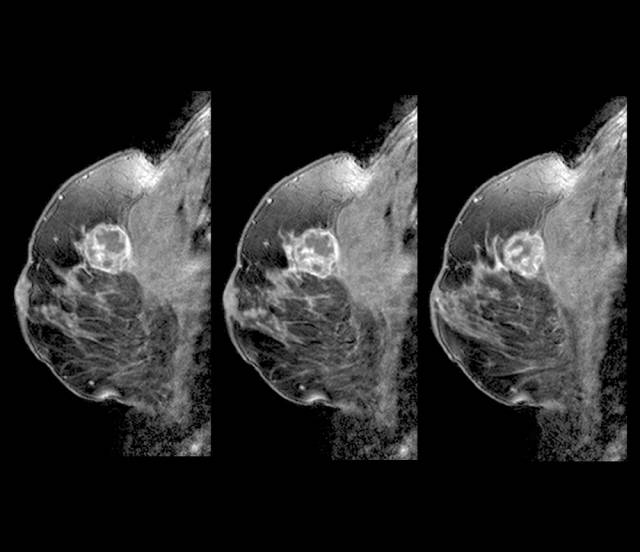

치밀유방은 유방 조직 내에 유즙을 만들어내는 유선 조직의 양이 많고 촘촘하며 지방이 적은 상태를 말한다. 치밀유방은 한국을 비롯해 아시아 국가 여성들에게 많다. 한국 여성의 70%가 치밀유방을 가진 것으로 알려져 있다. 유방은 크게 모유가 만들어지고 이동하는 유선이나 유관 등이 속하는 ‘실질 조직’과 이를 둘러싼 ‘지방 조직’으로 구성된다. X선을 활용한 유방촬영술에서는 실질 조직의 비중이 얼마나 되느냐에 따라 총 4단계로 구분하게 되는데, 그 중에서 유선 조직이 각각 50%, 75%를 초과하는 3~4단계를 치밀유방이라 부른다.

문제는 치밀유방이 유방암과 밀접한 관련이 있다는 점이다. 먼저 치밀유방은 유방촬영술을 활용한 유방암 진단에 어려움을 준다. X선 촬영 시 유방 내 지방 조직은 검게 투과되는 반면, 암이나 양성종양은 하얗게 나타나므로 이를 토대로 유방암 여부를 진단하게 된다. 그런데 실질 조직이 밀집돼 있으면 X선이 실질 조직을 투과하기 어려워 암이나 양성종양처럼 하얗게 표시된다. 이로 인해 유방 내 종양을 발견하기 어려워진다.

흔히 국가 건강검진에서 유방 X선 검사를 받았다는 이유로 충분하다고 여기는 사람도 적지 않은데 이는 절반만 맞는 이야기다. X선은 장비 특성상 미세석회로 발견되는 암을 찾아내는 데 활용도가 매우 높다. 하지만 유방조직이 밀집돼 있으면 X선이 투과하기 어려워 암이나 양성종양을 분명하게 구분하기 어렵기 때문에 치밀유방을 가진 경우에는 유방초음파도 병행하는 것이 바람직하다. 유방초음파는 방사선에 대한 노출 위험이 없고, 검사 민감도가 높아 X선으로 미처 발견하지 못한 유방암 병변을 찾는 데 도움을 줄 수 있다.